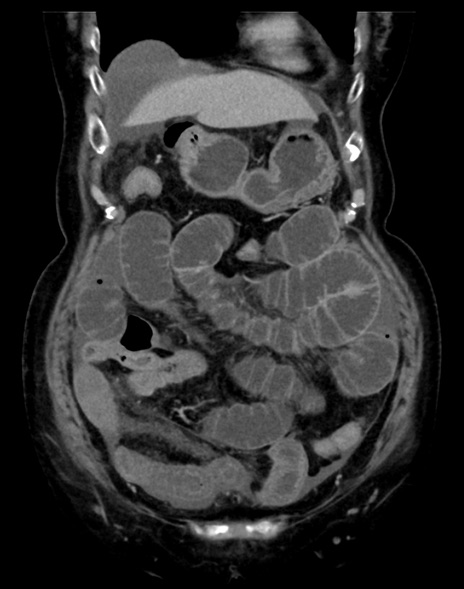

症例13 CT(冠状断像)1日半後